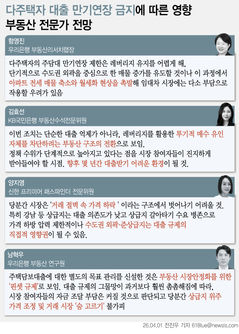

박상민 서울대병원 가정의학과 교수팀(김재원 연구원)은 서울대병원 건강증진센터에서 2004~2019년 동안 흉부 X선과 DXA(골밀도 검사) 검사를 모두 받은 여성 1만4502명의 데이터를 분석해 다양한 파운데이션 기반 AI 모델의 예측 성능과 설명 가능성을 비교한 연구 결과를 28일 발표했다.

골다공증은 뼈의 양이 줄고 구조가 약해지면서 골절 위험이 높아지는 질환으로, 고령화와 함께 환자가 빠르게 증가하고 있다. 그러나 표준검사인 DXA는 장비 접근성 등의 문제로 충분히 시행되지 못하는 경우가 많다.

반면 흉부 X선은 대부분의 건강검진에서 이미 촬영되므로, 이를 활용해 골다공증 여부를 함께 평가할 수 있다면 조기 진단의 새로운 대안이 될 수 있다. 다만 지금까지의 AI 모델은 예측 과정이 명확하게 설명되지 않는 '블랙박스' 문제 때문에 임상 적용에 어려움이 있었다.

연구팀은 먼저, 다양한 이미지에서 사전 학습된 파운데이션 모델(Foundation Model)을 의료 영상 분석에 적용했다. 파운데이션 모델은 대규모 데이터로 학습된 AI 모델로 이를 의료 영상에 맞게 미세 조정하면 제한된 의료 데이터로도 높은 성능을 낼 수 있다.

연구에는 일반 이미지로 학습된 모델(OpenCLIP, DINOv2)과 의료 영상으로 학습된 모델(CheXagent, RAD-DINO) 등 네 가지 모델이 사용됐다. ▲마지막 분류 단계만 새로 학습하는 '선형 검증' ▲모델의 일부 레이어만 재학습하는 '부분 미세조정 방식' ▲저차원 행렬을 추가하는 'LoRA 방식' 등 세 가지 방법을 적용해 총 12개의 AI 모델을 만들었다.

AI는 입력된 흉부 X선에서 척추와 늑골 같은 뼈 구조를 중심으로 특징을 추출하고, 이를 기존에 학습된 패턴과 비교해 정상(T-score ≥ -1.0), 골감소증(-2.5 < T-score < -1.0), 골다공증(T-score ≤ -2.5) 중 어떤 상태와 가장 유사한지를 판단한다.

연구팀은 여기에 더해 AI가 실제로 어떤 뼈를 근거로 삼아 판단하는지까지 확인할 수 있도록 '설명 가능성' 평가 체계를 설계했다. 뼈를 모두 가린 상태에서 특정 뼈 부위를 추가해 성능이 얼마나 향상하는지 확인하는 '차단 분석 방식'과 AI의 주목 영역이 실제 뼈 위치와 얼마나 일치하는지를 계산하는 '유의성 지도 방식'(IoUbone)을 통해, AI가 임상적으로 중요한 뼈 구조를 근거로 판단하는지를 정량적으로 검증했다.